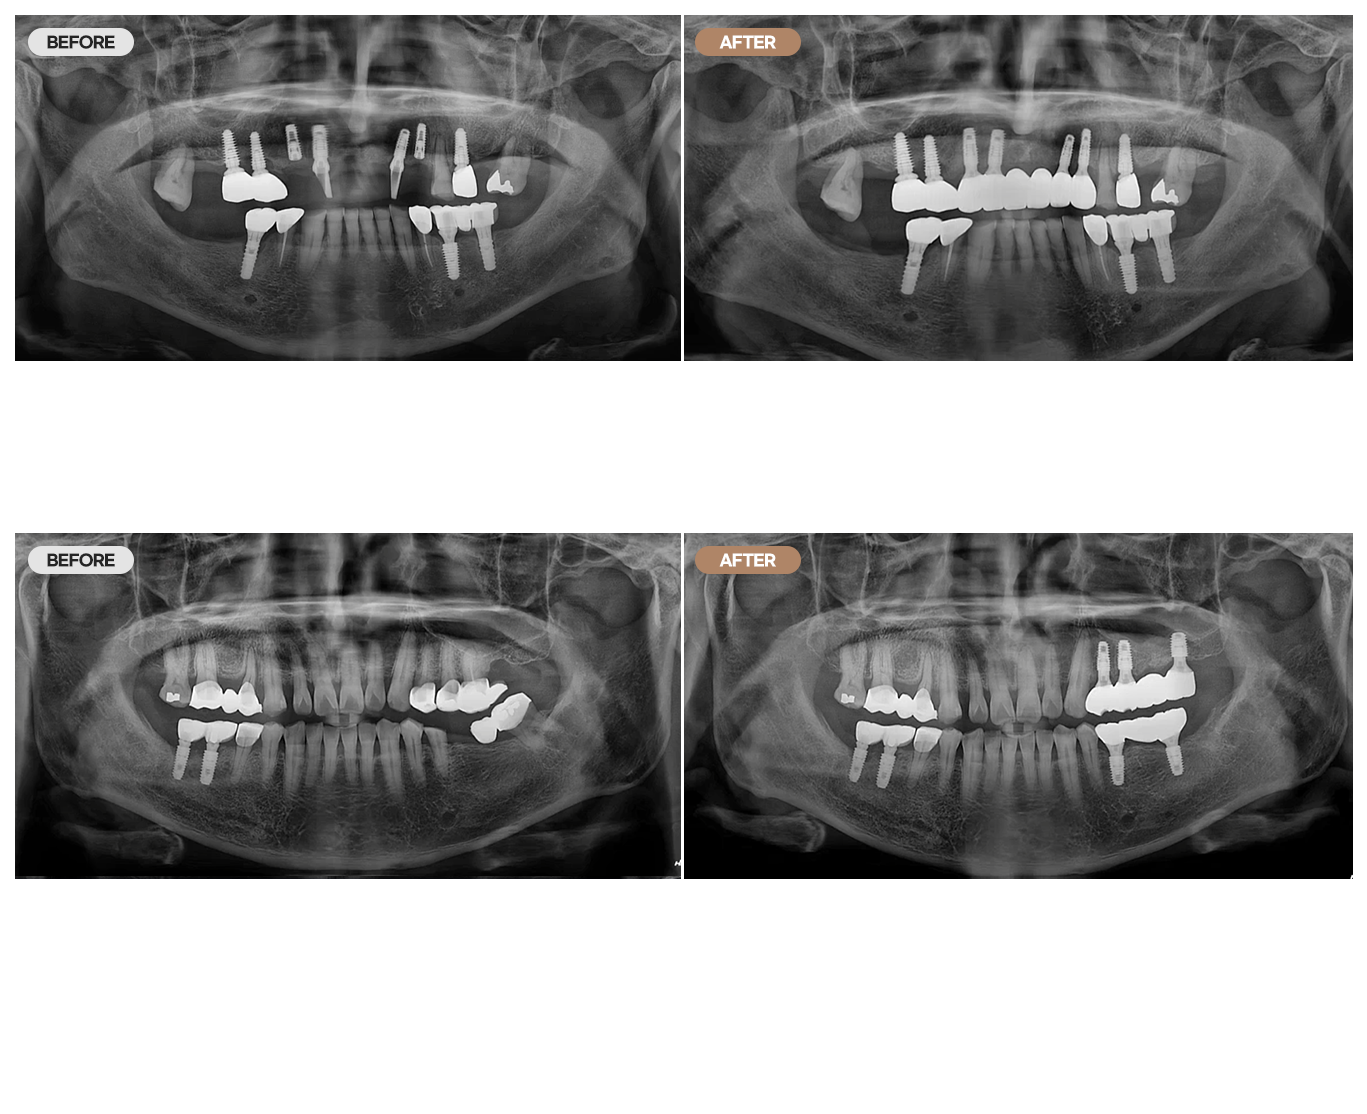

임플란트 CASE